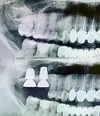

Implant tedavisi